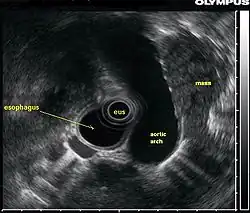

La ecografía endoscópica o ecoendoscopia es un procedimiento en el que se combina la técnica de endoscopia con el uso de ultrasonidos, obteniendo de esta forma imágenes de gran calidad de los órganos internos, sobre todo del esófago, estómago, páncreas y mediastino.[1] Si se combina esta técnica con la ecografía Doppler, los vasos sanguíneos cercanos a estas estructuras también pueden ser evaluados.

La ecografía endoscópica también puede ser utilizada para visualizar los ganglios linfáticos presentes en la cavidad torácica que rodean las vías respiratorias (bronquios), mediante la introducción de una sonda de ultrasonido endoscópico al esófago; esta técnica es muy útil para el diagnóstico de cáncer de pulmón. Otro método para realizar el ultrasonido de las vías respiratorias es, introducir la sonda endoscópica dentro de los propios bronquios, esta técnica es conocida como ecografía endobronquial.